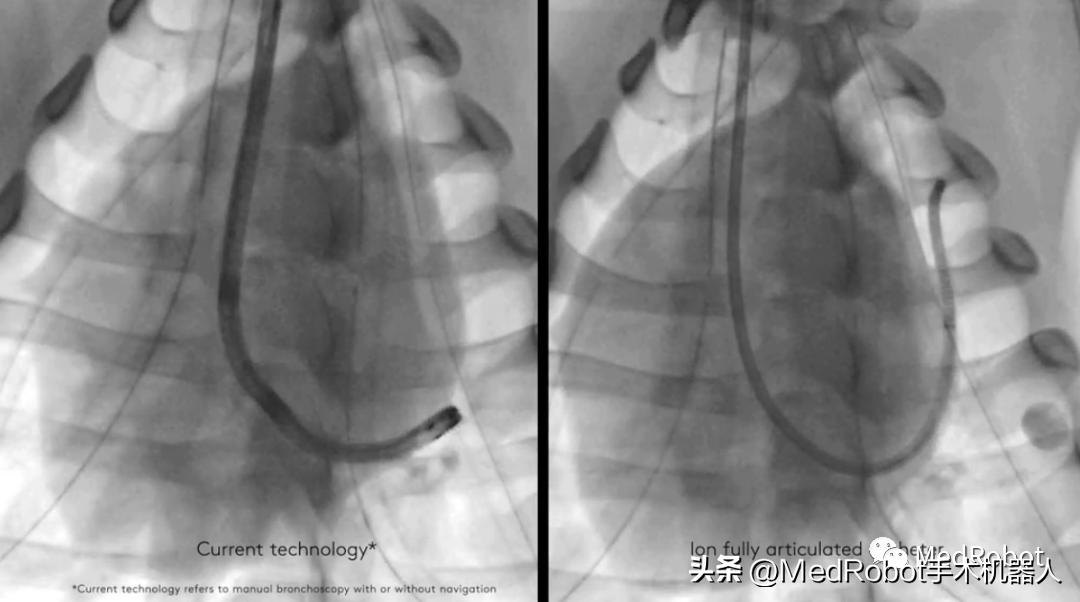

直观外科的Ion系统2019年2月份获得了FDA认证,实现肺内深处的微创活检。

Ion系统包括一个超细的人控机器人导管,可以让医生进入难以到达的呼吸道。形状感应技术,每秒数百次测量导管的整个形状,以便Ion系统的操作员在整个导航和活检过程中获得精确的位置和形状信息。Flexision柔性针与导管一起能够穿过曲折的气道,以便进行活组织检查。

形象一点来说,就像现实生活中用地图导航。医生如果在CT等影像中发现了藏于肺部偏僻角落的病灶,就需要带着工具精准的到达那个地方——实施肺部活检的过程就像我们驾车在惊险而未知的路途中到达目的地,而Ion是搭载着GPS导航系统又可以灵活移动的交通工具。Ion配备的外径为3.5mm的导管,至少可达到细支气管(G11-G13)。同时导管头部还可以进行180度的偏转,辅助医生在小而弯曲的气管中,导航导管到达病灶,通过专用的活检针穿过导管收集周围的肺部组织。

Ion的超细机械导管和先进的可操作性使导航远至周围的肺部,其2.0毫米工作通道和3.5毫米外径导管可以穿过难以导航的小气道到达肺的所有18个部位。Ion系统的外围视觉探针可在导航期间提供直接视觉,光纤传感技术让医生可以随时准确了解导管的精确位置和形状信息且不易受到干扰。